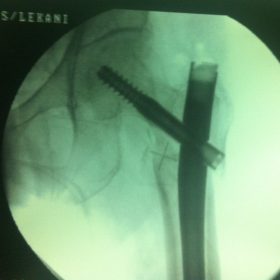

Διατροχαντήριο : Εξωαρθρικό κάταγμα, στην περιοχή ανάμεσα στο ελάσσονα και το μείζονα τροχαντήρα. Αντιμετωπίζεται χειρουργικά με ενδομυελική ήλωση τύπου γ-Nail. Δύο τομές 3 εκατοστών και 1 εκατοστού αντιστοίχως για την εισαγωγή και το κλείδωμα του ήλου μέσα στο οστό. Η μέθοδος είναι κλειστή,σχεδόν αναίμακτη,διάρκειας 30 λεπτών,με τη βοήθεια C-ARM (τηλεόρασης). Στον ασθενή παρέχεται οπτικό υλικό (όλα τα χειρουργικά στάδια) σε CD ή Στικάκι,λόγω της δυνατότητας καταγραφής του χειρουργείου από το C-ARM Ο ασθενής περπατάει άμεσα μετεγχειρητικά στις 5 ώρες μετά την επέμβαση και εξέρχεται από το νοσοκομείο σε 1 -2 ημέρες.

Υποτροχαντήριο :Εξωαρθρικό κάταγμα κάτω από τον ελάσσονα τροχαντήρα του μηριαίου οστού. Αντιμετωπίζεται χειρουργικά με ενδομυελική ήλωση τύπου Long γ-Nail. Δύο τομές 3 εκατοστών και 1 εκατοστού αντιστοίχως για την εισαγωγή και το κλείδωμα του ήλου μέσα στο οστό. Η μέθοδος είναι κλειστή,σχεδόν αναίμακτη,διάρκειας 60 λεπτών,με τη βοήθεια C-ARM (τηλεόρασης). Στον ασθενή παρέχεται οπτικό υλικό (όλα τα χειρουργικά στάδια) σε CD ή Στικάκι,λόγω της δυνατότητας καταγραφής του χειρουργείου από το C-ARM Ο ασθενής περπατάει άμεσα μετεγχειρητικά στις 5 ώρες μετά την επέμβαση και εξέρχεται από το νοσοκομείο σε 1 -2 ημέρες.